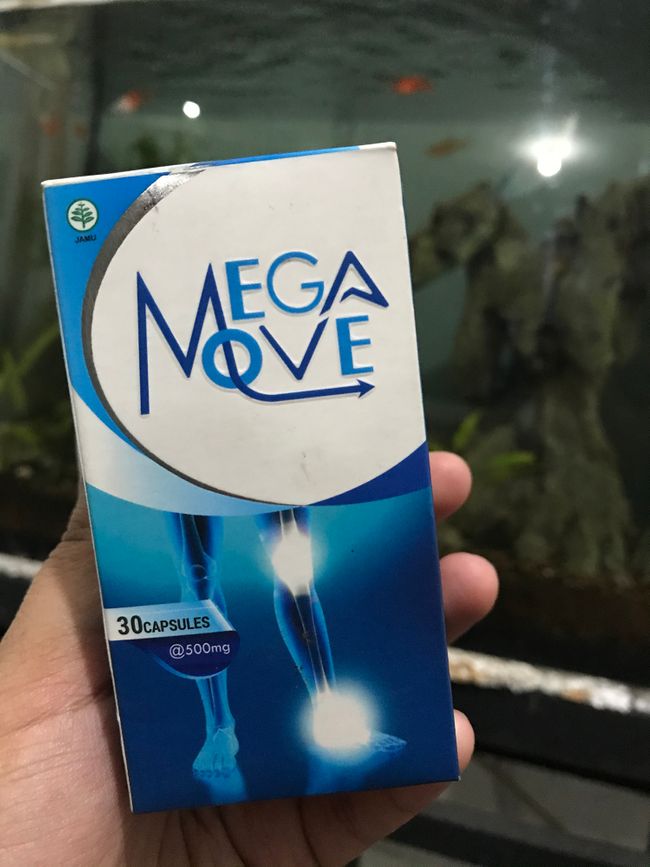

Dalam pencarian putus asa itu, saya mulai mencari solusi di internet. Di salah satu forum, saya menemukan sebuah postingan dari seorang pria yang menceritakan bagaimana ia berhasil mengatasi masalah sendinya. Yang mengejutkan, dia tidak menjalani operasi, tidak menerima suntikan, bahkan tidak perlu mengonsumsi pil pereda nyeri. Dia hanya mengandalkan satu bubuk ajaib! Bubuk itu, menurutnya, sangat ampuh dan bernama - Megamove.

Karena sudah lelah dengan berbagai pengobatan yang tak membuahkan hasil, saya memutuskan untuk mencoba. Harganya cukup terjangkau, dan yang lebih meyakinkan, komposisinya 100% alami. Sampai saat itu, saya sudah menghabiskan begitu banyak uang untuk mencari penyembuhan, jadi mencoba satu solusi lagi terasa sepadan.

Saya segera menghubungi pria yang menulis postingan tersebut dan bertanya di mana ia membeli Megamove. Ternyata, produk ini diproduksi dalam jumlah terbatas karena proses pembuatannya yang cukup rumit. Bubuk ini hanya dijual melalui situs resmi produsennya, dan stoknya pun sering kali cepat habis karena tingginya permintaan.

Jika Anda penasaran dengan produk yang sangat membantu saya, itu adalah bubuk untuk sendi bernama Megamove.

Megamove terbukti lebih efektif dibandingkan dengan suplemen sendi lainnya.

Megamove

100% bahan alami;

Menyembuhkan sendi secara menyeluruh;

Efek yang bertahan lama;

Melembapkan dan mencerahkan kulit;

Memperbaiki dan memperkuat rambut;

Membantu menurunkan berat badan;

Tanpa efek samping;

Harga terjangkau.

Megamove adalah terobosan nyata dalam dunia medis. Penggunaannya telah diuji secara klinis dan terbukti efektif melalui puluhan penelitian, hak cipta, dan bertahun-tahun uji coba. Formula inovatif dalam Megamove telah diuji klinis dan terbukti melalui puluhan penelitian, hak cipta, dan bertahun-tahun uji coba. Formula inovatif Megamove membantu mengembalikan jumlah cairan sendi dan mendukung fungsi normal sendi, menghilangkan rasa sakit dan ketidaknyamanan saat bergerak.

Bubuk ini mengandung bahan-bahan alami yang dirancang untuk meningkatkan kesehatan sendi. Kombinasi sempurna antara bahan alami dan tingginya kandungan peptida kolagen serta L-glutathione menjamin hasil terbaik. Setelah mendapatkan hasil yang positif dari penelitian klinis, perusahaan kami memutuskan untuk memulai produksi massal dan menjual Megamove di Indonesia.